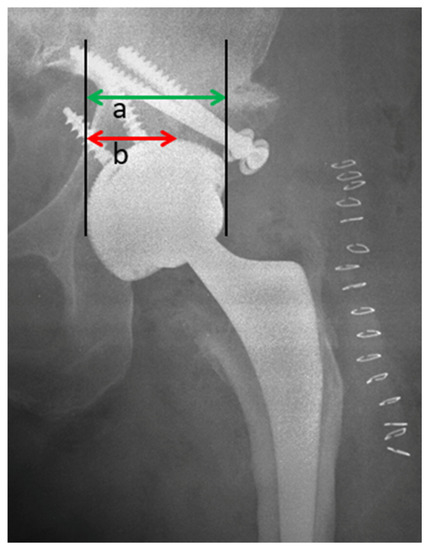

2.2. Radiological Assessment

3.2. Radiographic Results